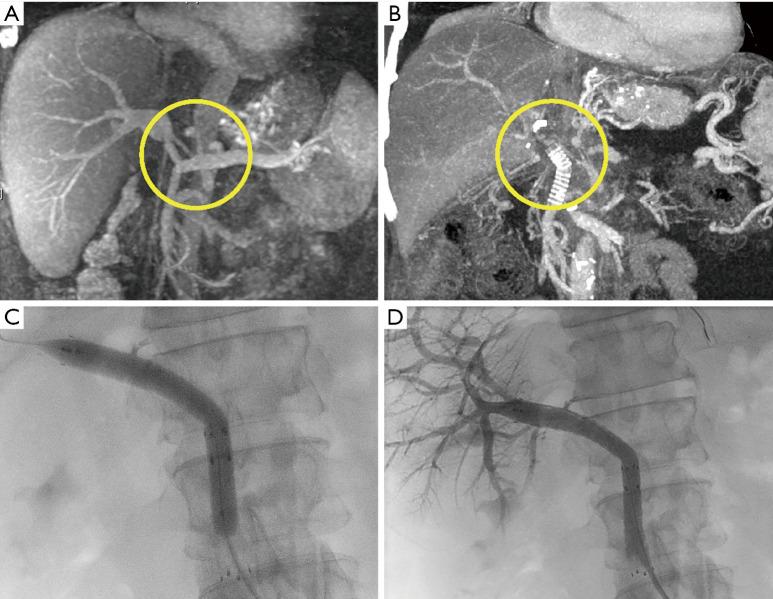

Hepatobiliary Surg Nutr. 2023 Dec 1;12(6):966-974. doi: 10.21037/hbsn-23-410. Epub 2023 Nov 15.